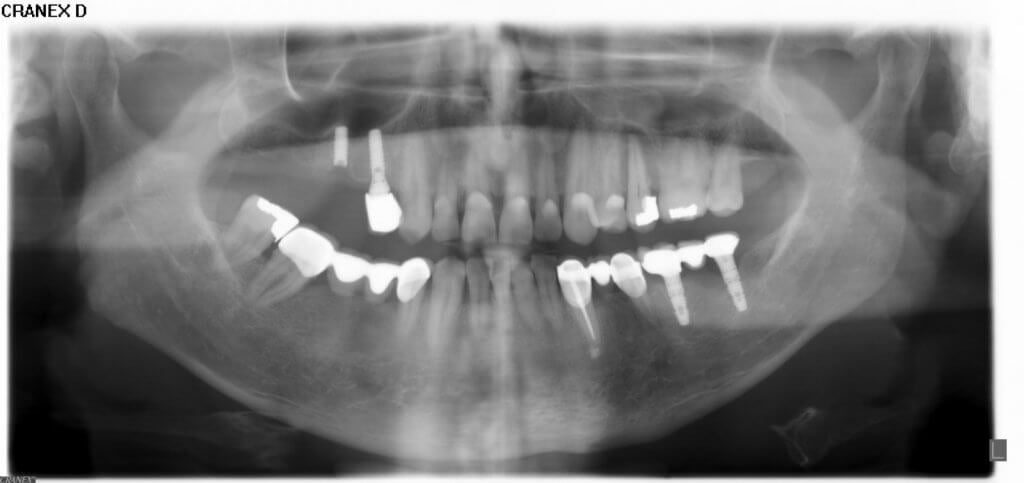

Tam dişsiz hastalar için implantlar büyük ölçüde çüpneme konforu sağlar ve yaşam kalitesini arttırırlar. İmplantlar ile ağızda hareket etmeyen stabil protez veya sabit köprüler uygulanabilir.